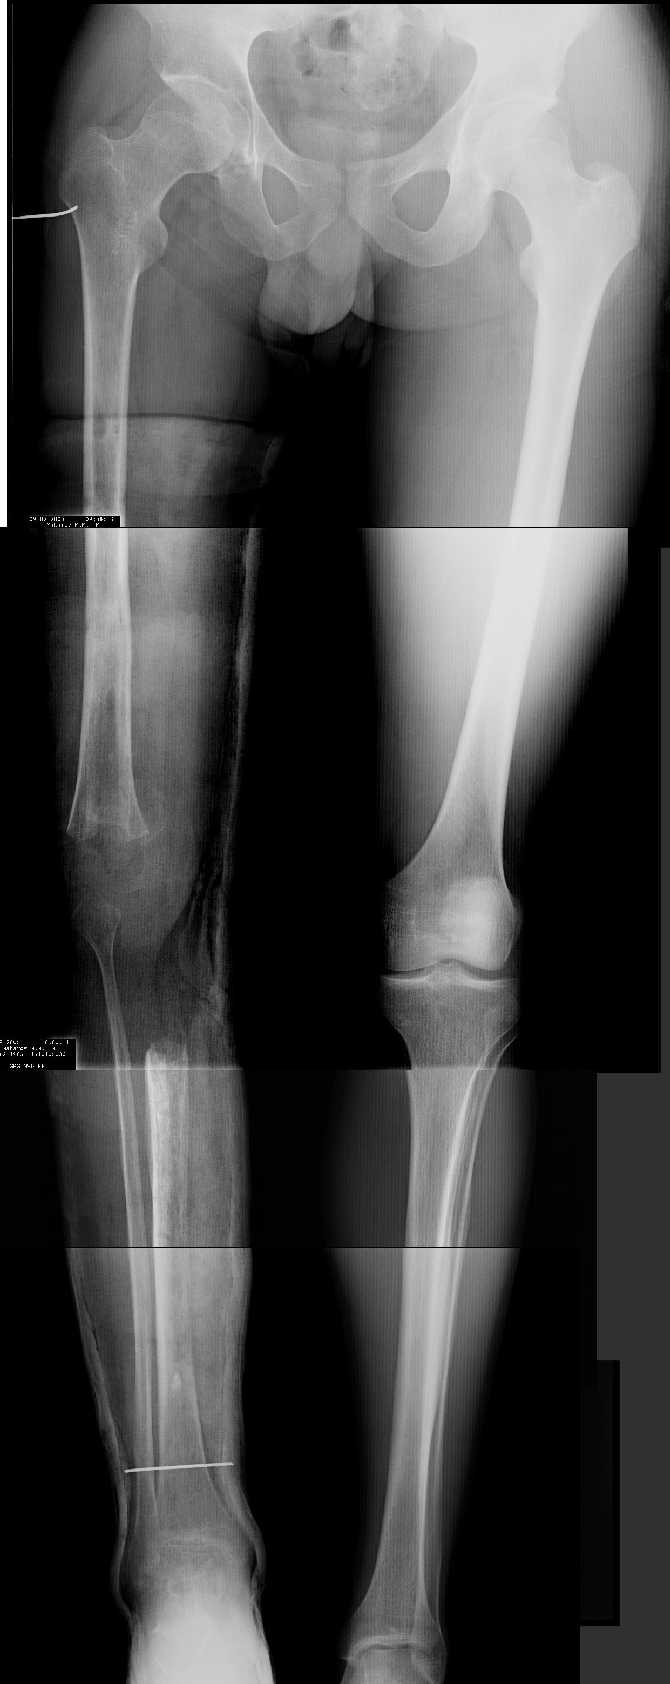

1. Иллюстрации - во вложении.

Два бедра после эндопротезирования.

Авторы операции долго думали почему больная хромает.

Сдклали снимок - одна нога короче почти на 3 см.

Здоровый человек и то будет хромать.

2. Другой пример - дефект после инфицирования коленного эндопротеза.

Предполагалось, что величина дефекта 11-12 см. Так получается, если

сделать снимок только области коленных суставов. Определить

укорочение сложно, так как нога просто болтатется.

Сделали снимок "от и до" - величина дефекта 17 см.

Правда эта иллюстарция сделана на цифровом рентгеновском аппарате.

Больной стоит, а трубка передвигается сверху вних, последовательно

выполняя рентгенограммы. В данном случае - 4 штуки.